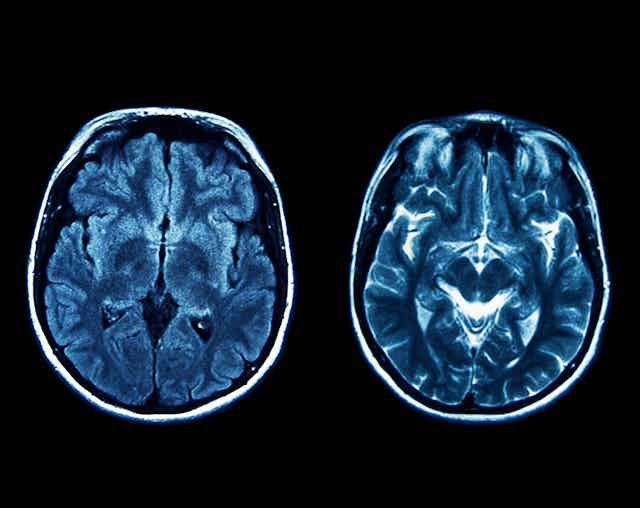

However, habenula research in humans has lagged behind animal studies. Consequently, until recently, the hyperactive habenula theory of depression had never been tested directly. In part this is because measuring the tiny habenula in humans is technically very difficult and requires a special high-resolution brain imaging method (to rule out the possibility that any results could be contaminated by activity in nearby regions).

We tested 25 people with depression, none of whom were taking any medication, and compared them with 25 never-depressed healthy volunteers. The participants underwent various high-resolution brain scans. Based on the theory described above, we predicted that the depressed participants would have a hyperactive habenula, either in the “resting-state” (lying in the scanner doing nothing) or evoked (by expectation of an electric shock), or possibly both. But our predictions were wrong.